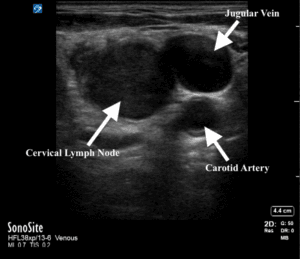

Point of Care Ultrasound (POCUS) was performed using the linear, high-frequency 12 Mhz probe by one of the authors as shown in Figures 2 and 3.

Figure 2. POCUS of neck mass level VB.

In the left neck level VB there was a large solid mass 3.4 cm x 4.1 cm. Rounded in shape with regular borders. Vascularity was increased. There was a maintained central echogenic hilum but also other abnormal increased echogenicity centrally. There was no fluid collection or evidence of abscess formation.

Normal lymph nodes should be discrete, well-defined, hypoechoic bean or oval shaped structures. They should have distinct borders and a short axis-to-long axis ratio of less than 0.5. The central echogenic hilum should be readily appreciable [1].

A lymph node with an abscess, however, loses its architectural integrity often appearing more circular, occasionally with variable degrees of internal echoes and lacking internal vascular flow.

An enlarged lymph node with a more rounded appearance, i.e. an increase in diameter in the short axis, should be carefully interrogated. Thickened or irregular walls, loss of the normal echogenic hilum or internal features such as increased echogenicity (suggesting calcification, other infiltration or internal cystic change) should prompt the user to consider a potentially sinister cause such as the algorithm in Figure 7 demonstrates [2] .